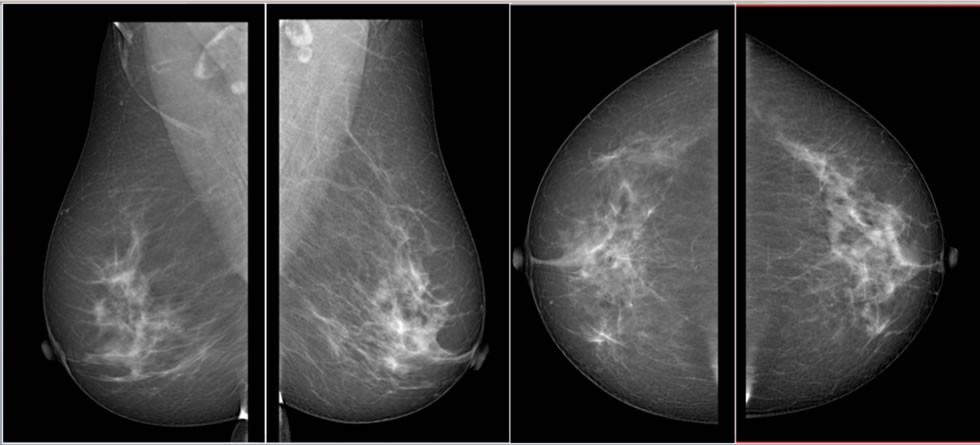

Interpretación de Estudios de Radiología Convencional

La interpretación de los estudios de radiología en formato convencional y digital es realizada por profesionales con...

Leer más -